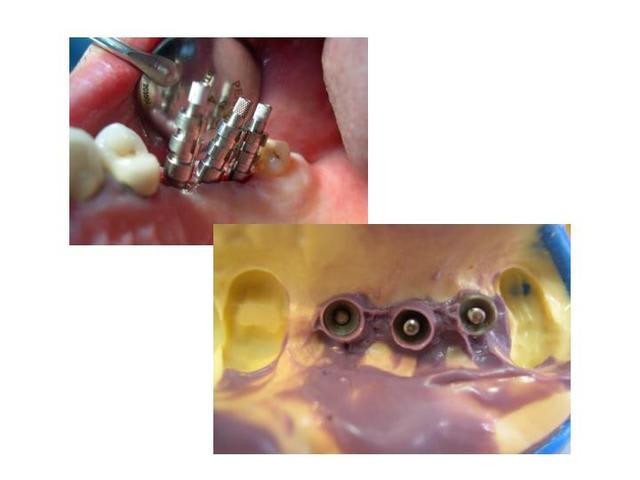

voilà, pour revenir à ce qu'on disait: une petite illustration: 25 et 27 ont été extraites. et voici la suite.

et la suite

Implants iwsvxa - Eugenol